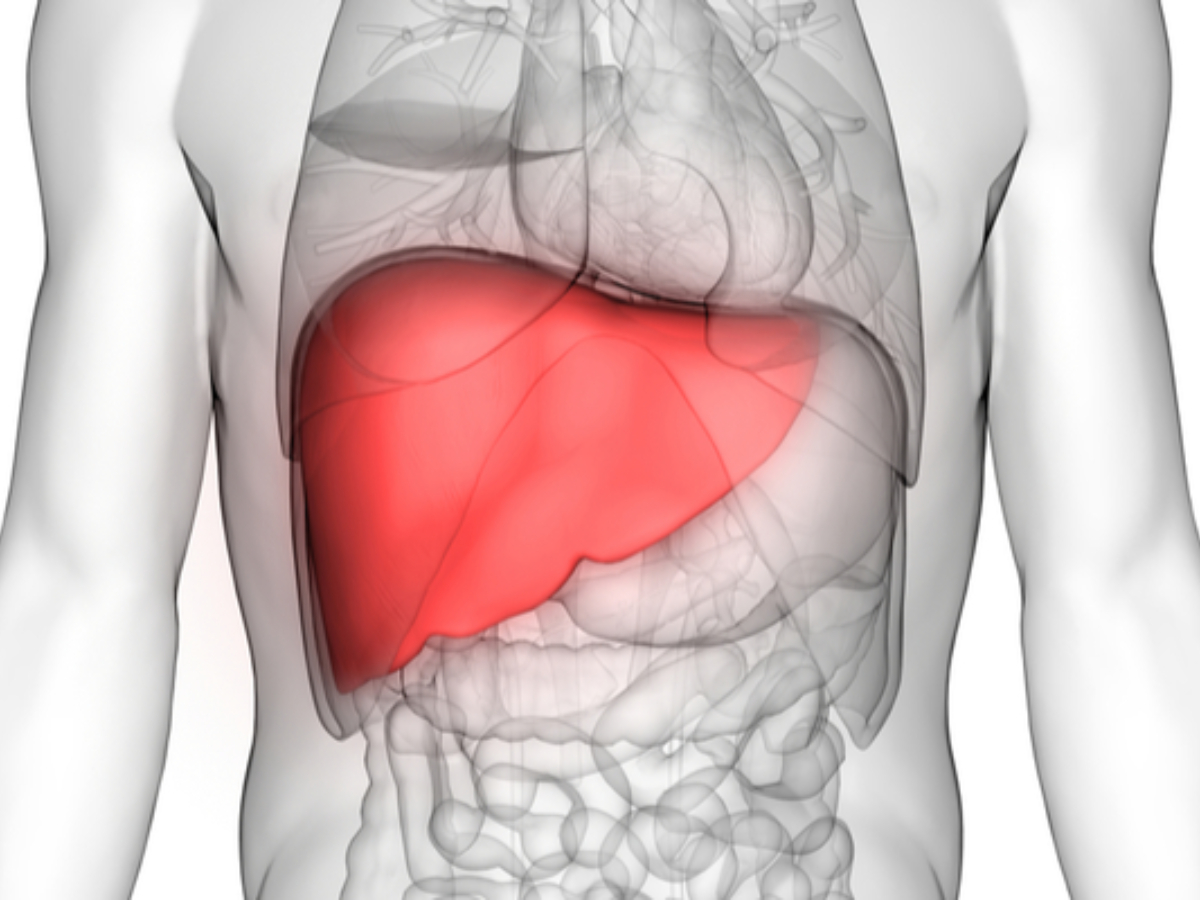

फैटी लिवर की समस्या

फैटी लिवर की समस्या दूर करने के लिए ये कपालभाति काफी उपयोगी होती है. इसको करने से शरीर की गंदगी दूर होती है और ताजगी मिलती है.